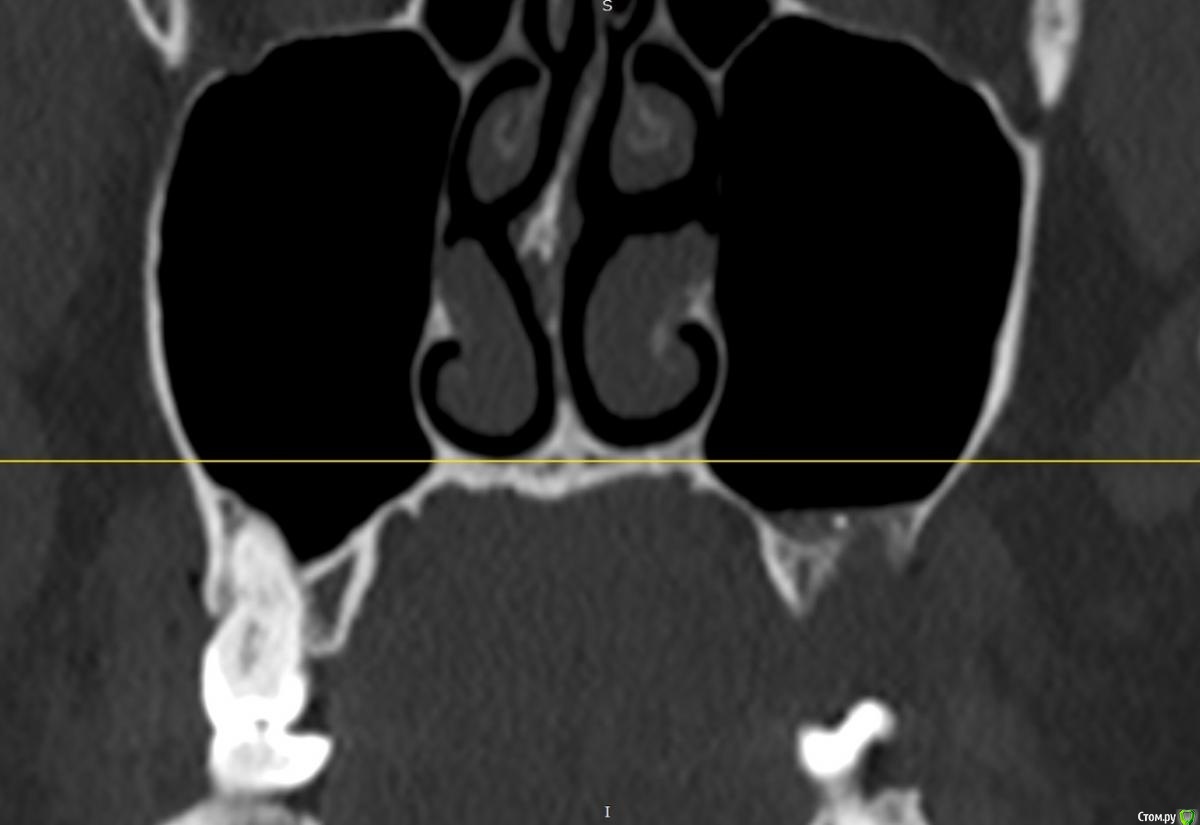

Фрагмент кости в гайморовой пазухе. Нет гноя. Причина болей?

Здравствуйте. На протяжении 5 месяцев беспокоит боль в области между левой пазухой и челюстью. Боль острая, ноющая как при боли в зубе. Верхняя 7а слева (депульпированная) удалена месяц назад, но боль только усилилась. Со временем стали болеть и все суставы в теле, в особенности руки и ноги. Выполнять простые движение стало очень больно. На КТ видны инородные фрагменты и нарушение целостности нижней стенки пазухи, но в Спб никто их не захотел удалять инородные фрагменты из-за того, что причина боли по мнению врачей не в этом. В результате боль только усиливается. Причину боли при моей картине КТ никто установить не может. Обращалась почти во все клиники. Несколько неврологов патологию лицевого нерва исключили. Все это время держится температура 37-37,5. Ощущение сильного воспалительного процесса, боль немного стихает на приеме антибиотиков, но ненадолго, примерно на неделю - две. Обычные обезболивающие совершенно не помогают. Жевать пищу очень больно, сильно рот не открыть. Слабость и нет аппетита. Может ли так организм реагировать на инородный фрагмент кости в пазухе или дело в другом? Возможно ли что есть какие-то нарушения (переломы, трещины и пр) кости, которые требуют хирургического вмешательства?Вопрос возник по той причине, что при промывании пазухи есть ощущение проникания жидкости куда-то за пределы слизистой и после промывания состояние заметно ухудшается. Если кто-то может помочь советом буду очень признательна. Есть несколько КТ 3д. https://yadi.sk/d/PX30GoO1Cn5m_w -  от 13.06.2020 (примерно сразу после появления болевого синдрома), https://yadi.sk/d/bm7FD9SYVw2-Gw- сразу перед удалением зуба,  https://yadi.sk/d/fbaOTQT2-ya4xQ - КТ пазух от 21.11.2020 (то что есть на сегодня).